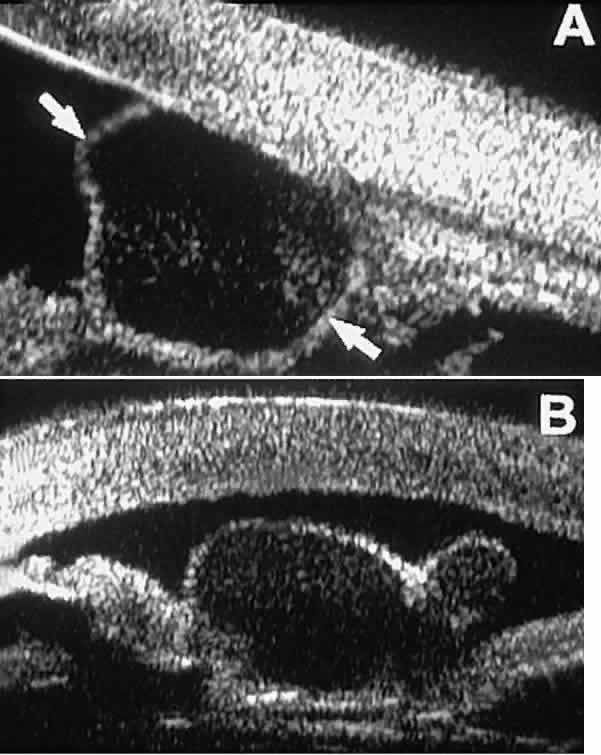

Cystic lesions of the iris and ciliary body can be of four types: primary neuroepithelial cysts, stratified squamous epithelial cysts, neuroepithelial cysts associated with solid tumors, and intratumoral cavities.15 Primary neuroepithelial cysts (see Fig. 22) are very distinct on UBM imaging. These lesions consist of a central sonolucent cavity surrounded by a thin wall of highly reflective neuroepithelial cells. They arise from the posterior surface of the iris (see Fig. 22A), in the iridociliary sulcus (see Fig. 22B and C), or from the inner aspect of the ciliary body (see Fig. 22D). They are often multifocal (see Fig. 22C and D) and bilateral.15 The largest lesions of this type typically occur in or near the horizontal meridians.

Stratified squamous epithelial cysts (Fig. 23) are almost exclusively unilateral and unifocal,15 have substantially thicker walls than do primary neuroepithelial cysts, and usually contain prominent intracavitary particles (desquamated epithelial cells). Almost all such cysts involve the peripheral iris and angle region. Such cysts are usually secondary to prior ocular surgery or laceration in which conjunctival epithelial cells were implanted into the iris stroma.

Fig. 23. UBM features of stratified squamous epithelial cysts of iris. A. Thick-walled implantation cyst of stratified squamous epithelium replacing normal iris. Note intracavitary particles. B. Bilobed stratified squamous epithelial inclusion cyst of iris with prominent intracavitary particles.

Secondary neuroepithelial cysts occur rather frequently in association with solid tumors of the iris or ciliary body.15 On UBM (Fig. 24), such cysts appear quite similar to the primary neuroepithelial cysts described above; however, they are associated with a solid mass arising within the iris or ciliary body.

Fig. 24. UBM appearance of neuroepithelial cysts associated with solid tumors of the iris and ciliary body. A. Single neuroepithelial cyst associated with iris melanoma. B. Multiple neuroepithelial cysts associated with iridociliary melanoma.